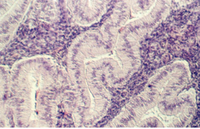

Pseudostratified columnar epithelium